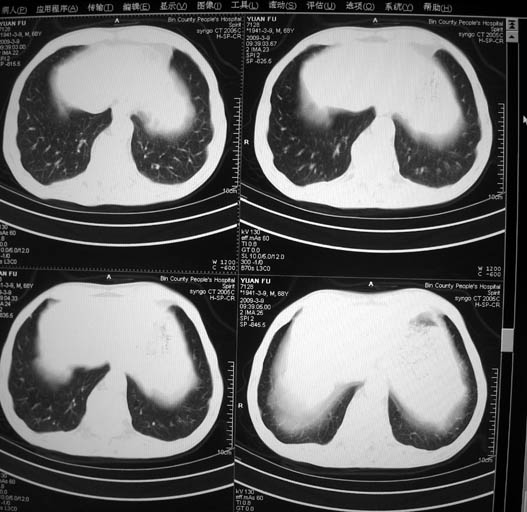

标题: CT18577:男,68岁,左肺占位。 [打印本页]

标题: CT18577:男,68岁,左肺占位。

男,68岁,左上肺占位,肺门淋巴结转移?

1)考虑左肺上叶尖段周围型肺癌并阻塞性肺炎,纵隔淋巴结转移。2)心包少量积液。

左上肺周围型肺癌伴肺门淋巴结转移

左上肺周围性肺癌伴纵隔淋巴结转移